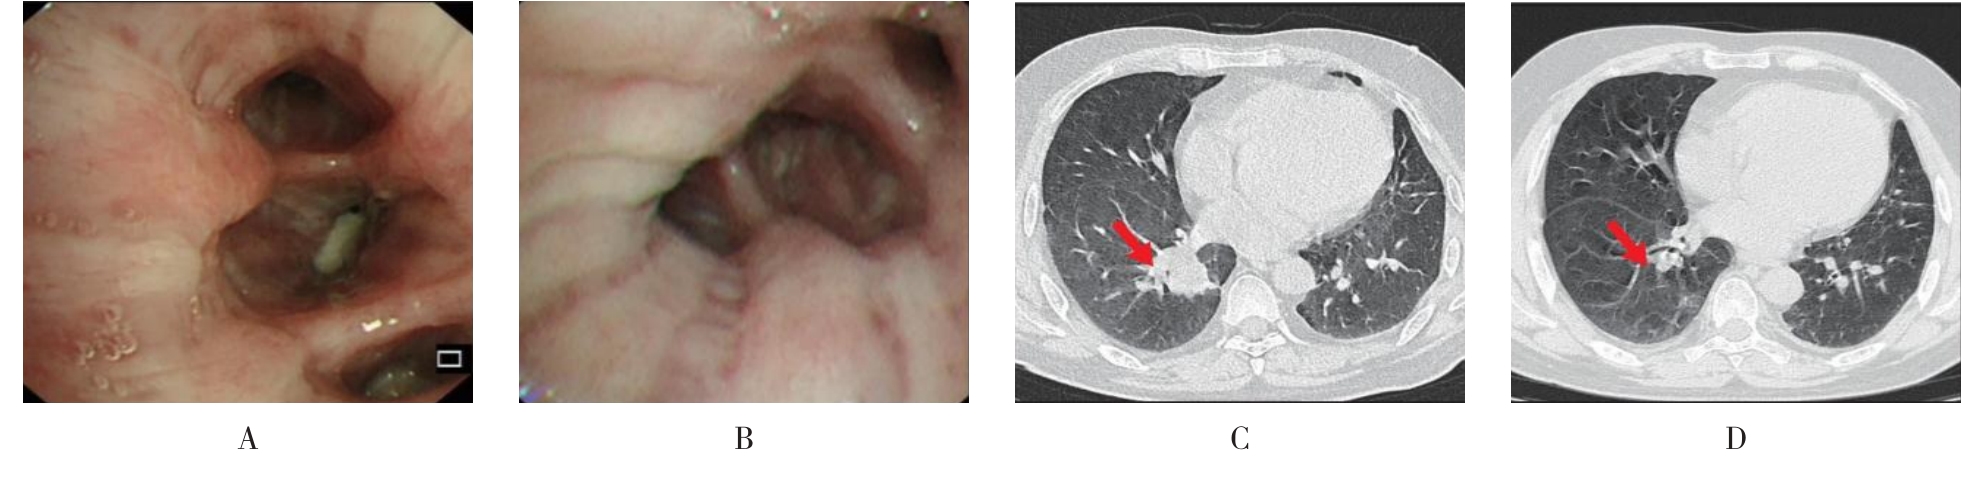

• 侵袭性肺真菌病的支气管镜表现及介入治疗效果

2025, 31(9):81-90. DOI: 10.12235/E20250317

摘要 (112) HTML (56) PDF 6.06 M (77) 评论 (0) 收藏

摘要:目的 探讨侵袭性肺真菌病(IPFD)的支气管镜表现,并评估介入治疗的安全性和疗效。方法 回顾性分析2018年5月12日-2025年5月12日于该院行支气管镜检查的35例IPFD患者的临床资料,观察IPFD的支气管镜表现及介入治疗效果。结果 共收集35例患者临床资料。其中,男22例,女13例,患者年龄(53±14)岁。基础疾病包括:血液系统恶性肿瘤10例,长期应用糖皮质激素者5例,2型糖尿病者4例,肺部恶性肿瘤2例,器官移植1例。胸部CT显示:肺部病变累及单肺叶者19例,累及多肺叶者16例。支气管镜下表现主要为:黏膜充血水肿29例(82.9%)、坏死物堵塞管腔22例(62.9%)、大量黏稠脓性分泌物17例(48.6%)、支气管部分狭窄或闭塞16例(45.7%)、黏膜坏死9例(25.7%)、黏膜出血5例(14.3%)、真菌球3例(8.6%)。其中,32例(91.4%)接受全身性抗真菌治疗,17例(48.6%)接受支气管镜局部两性霉素B灌注治疗,10例(28.6%)采用活检钳钳除病灶,6例(17.1%)采用冷冻探头冻取病灶,4例(11.4%)接受氩气刀治疗。28例(80.0%)临床症状明显改善,肺部影像学病灶缩小或消退;4例(11.4%)病灶稳定;3例(8.6%)未完成治疗。结论 IPFD多见于免疫抑制宿主,支气管镜常表现为:坏死物堵塞管腔、伴脓性分泌物、支气管管腔狭窄和局部黏膜充血水肿或坏死。全身抗真菌药物联合支气管镜下介入治疗,安全性高,且疗效好。